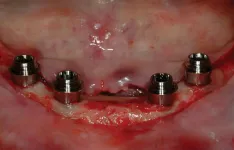

All-on-4 advocates claim that this type of treatment plan reduces cost and saves treatment time, but with the introduction of the ScrewIndirect one-piece implant that provides the implant, abutment, comfort cap, and transfer at a fraction of the cost of the implant alone from all the major implant companies, the economics argument for using the minimum number of implants is no longer valid. The ScrewIndirect screw-receiving platform allows splinting of implants that have up to 40 degree divergence, allowing distal angulations of up to 20 degrees if desired. Placement of five implants in the lower symphysis and six anterior to the maxillary sinuses can be relatively straight and still support adequate length of distal cantilevers. Four ScrewIndirect implants can also be placed, as shown below, splinted with a distal attachment for retention of an overdenture, but providing the patient with a fixed-detachable prosthesis that eliminates the need for a removable prosthesis is a more natural solution to restoring an edentulous jaw.

The ScrewIndirect one-piece implant offers a 3.0 mm D implant with adequate strength. All four diameter options (3.0 mm, 3.7 mm, 4.7 mm and 5.7 mm) have the same 5 mm D multi-unit platform. The 3.0 mm D implant allows treatment of narrow ridges and simplifies accurate placement during flapless surgery. Providing teeth in one day to edentulous patients and immediate implant placement following extractions is becoming the treatment of choice. The patient's existing denture is converted to a fixed-detachable prosthesis immediately following implant placement. This is accomplished by attaching titanium sleeves to the implants that project through holes cut in the denture and attached them to the denture with cold-cure acrylic followed by shortening the denture flanges.